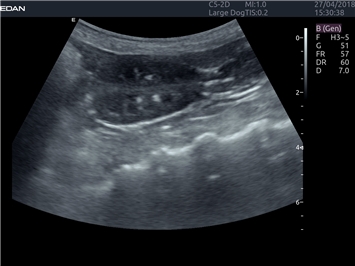

EDAN Acclarix LX4 VET представляет собой профессиональную ультразвуковую систему, специально разработанную для ветеринарных исследований. Сочетание стабильности, высокой производительности и эффективности делает эту систему идеальным выбором для современной ветеринарной практики.

Передовые технологии визуализации:

• Адаптивная визуализация тканей:

• Оптимизация изображения для различных видов животных

• Улучшенная детализация структур

• Универсальные датчики для различных видов животных

• Специализированные предустановки для ветеринарных исследований